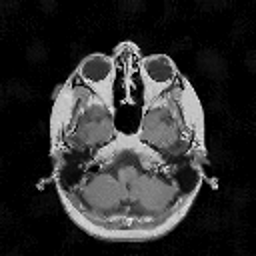

VII-C Experiments with real-life data

Reconstruction of real-life MRI images has been the next step in our comparative study. To this end, the data set of [19] have been used herein. The data were obtained at the University Hospital of Ghent and it is publicly available at http://telin.ugent.be/~sanja/Sanja_files/Software/MRIprogram.zip. The data contains a sagittal and an axial scan of a human brain, which are shown in Fig. 10 and Fig. 11, respectively.

The reconstruction results obtained for each of the tested images using the proposed and reference methods are shown in Subplots (b)-(f) of Fig. 10 and Fig. 11, respectively. From these figures, it can be seen that the proposed algorithms result in higher-contrast reconstructions of better visual clarity as compared to the reference approaches. The difference is particularly evident for the case of Fig. 11, where the proposed algorithms result in less noisy images, while exhibiting higher effective resolution and contrast.